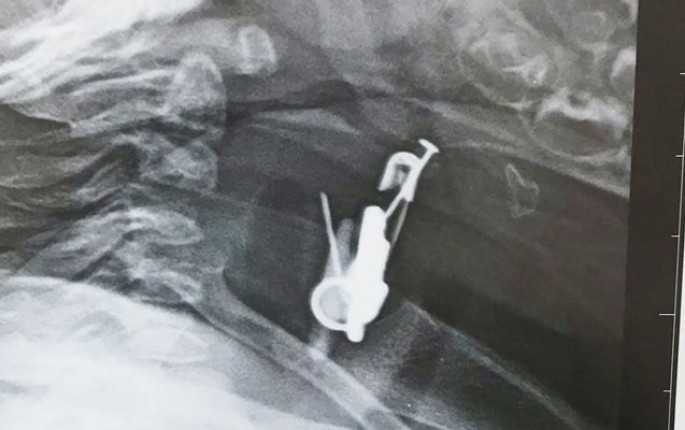

Azərbaycanda altı aylıq körpənin mədəsindən sancaq və digər cisimlər çıxarılıb. Avtosfer.az-ın Trend-ə istinadən məlumatına görə, hadisə Biləsuvar rayonunda baş verib. Belə ki, sözügedən rayonda valideyn yeni doğulan oğlan uşağına gözdəyməyə qarşı daş və ələmi sancaqla onun paltarına taxıb. Bir müddətdən sonra altı aylıq körpənin vəziyyəti pisləşib. Uşaqda iştahsızlıq və tənəffüs çatışmazlığı qeydə alınıb. Valideyn tərəfindən Bakıya xəstəxanaya çatdırılan uşağın mədəsində yad cismin olduğu məlum olub. Belə ki, altı aylıq körpə sancağı və üzərində olan digər əşyaları udub. Ə.F.Qarayev adına 2 saylı uşaq kliniki xəstəxanasında endoskopik üsul ilə körpənin mədəsindən həmin əşyalar çıxarılıb.